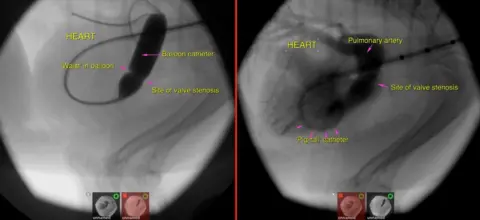

They had to wait until he was 5lb (2.4kg) to insert a balloon catheter.

Dick White ReferralsA small balloon catheter was inserted and inflated in the malformed valve to take the pressure off his heart.

"The procedure presented significant challenges because of the extremely small size of the patient," Mr Wray said.